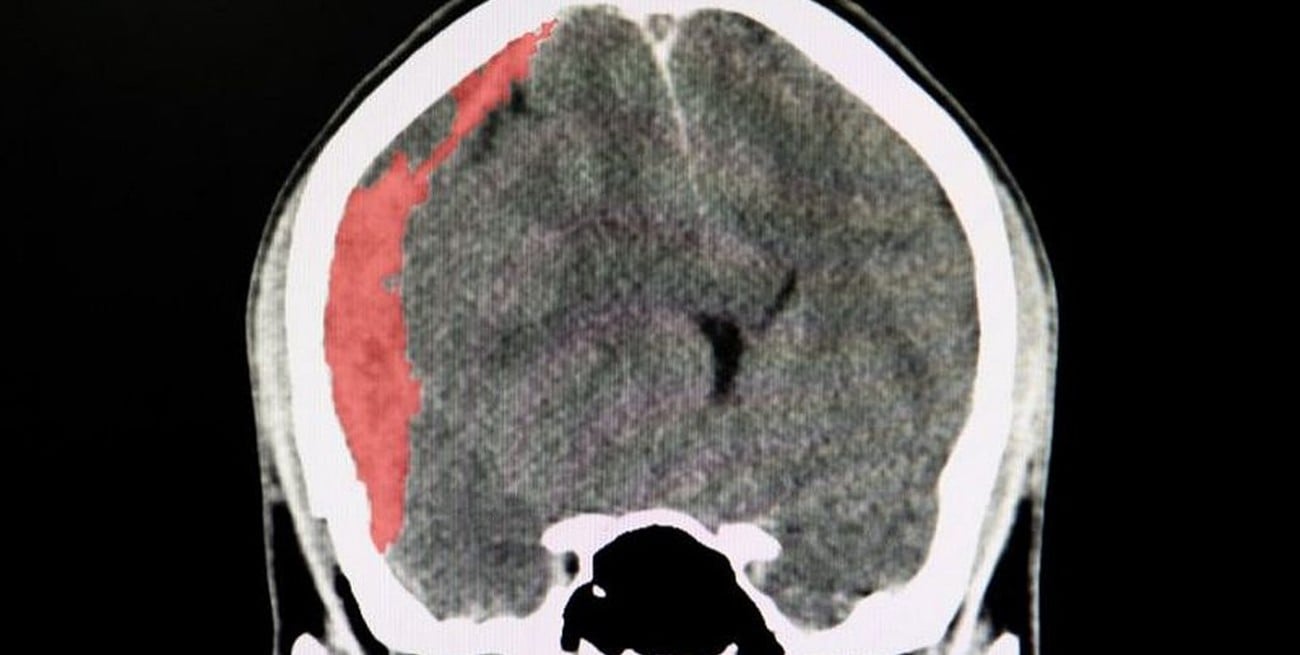

El hematoma subdural crónico se da entre la duramadre y el cerebro, y se pueden presentar por traumatismos de cráneo, algunos banales o por una desaceleración brusca, y se presentan en la parte externa del cerebro muchas veces en pacientes anticoagulados o antiagregados.